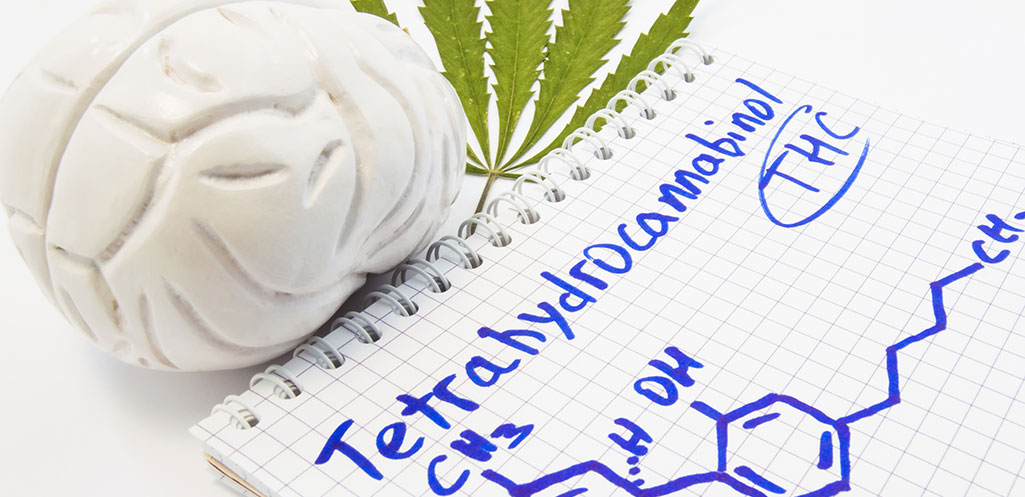

Marijuana impairment, and particularly how long impairment lasts, is often misunderstood, primarily because advocates for marijuana typically present data from available studies within a narrow scope that aligns with their position.